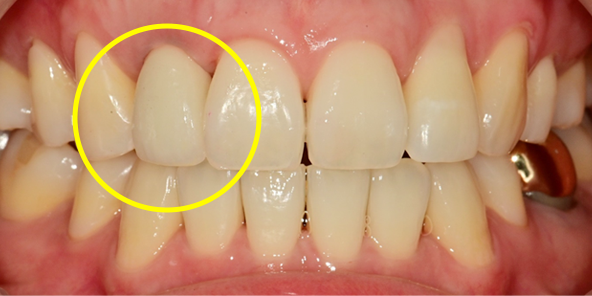

내원 당일 이루어지는 임플란트 기술력! 하루 완성 임플란트는 당일에 식립하고

임시 보철물까지 완성됩니다.

일상생활이 가능하도록 임시 보철물 완성

당일 수술 후 보철물을 붙이는

네비게이션 임플란트 방식입니다.